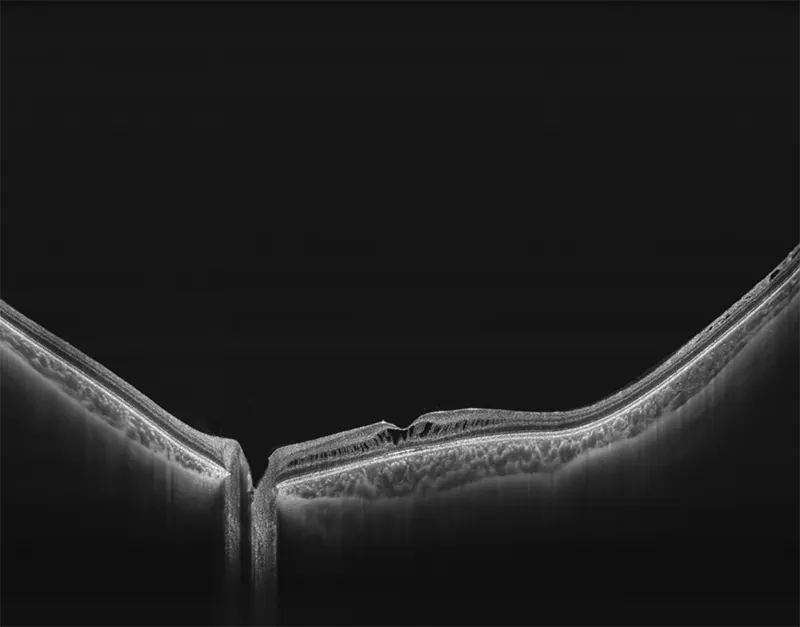

BMizar (BM-400K) es el OCT más potente de la industria con una fuente de barrido de 400 kHz. Su excepcional diseño óptico eleva la experiencia de la Angiografía OCT a un nivel sin precedentes. Con imágenes de alta definición de la retina, la coroides y el segmento anterior, cubre sin esfuerzo un área increíblemente grande en un solo escaneo (logrando un OCTA de 24 mm de ancho en solo 7-15 segundos).

Galería OCTs del TowardPi BMizar